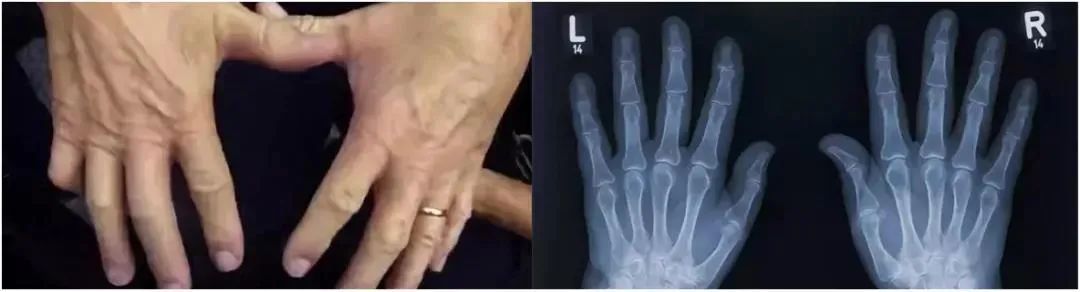

他为了证明妈妈说的“再掰会得关节炎的!”是假的,于是开始了连续50年的“掰手指”实验:

每天掰一掰自己的左手

50年后,唐纳德博士给自己的左右手照了X光,发现左右手并无差别,都很健康。

后来又有科学团队对掰手指进行研究,发现掰手指的咔嗒声其实是来自关节腔里气泡的形成和破裂,并不是关节摩擦导致的。